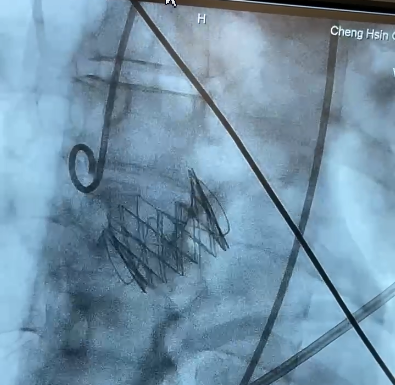

经右侧股静脉置入临时起搏器,经右侧股动脉在患者主动脉无冠窦内放置1根6F猪尾导管定位。透视下定位后第五肋间小切口进胸,打开心包,选择心尖裸区缝制六边形荷包。心尖穿刺后将泥鳅导丝过主动脉瓣经升主动脉、主动脉弓到达降主动脉膈肌水平,通过TEE确认细导丝没有与二尖瓣腱索缠绕。单弯管交换硬导丝后,用16F扩张鞘预扩心尖穿刺处,后将 J-Valve瓣膜(25mm)装入输送器。将输送器推送至主动脉根部,释放定位件,适当调整定位件角度使其进入三个主动脉窦部,并通过DSA和TEE确定三个定位件准确入窦后完全释放瓣膜,撤出输送器。通过DSA和TEE观察人工瓣膜膨胀后金属支架的形态、位置良好,无瓣周漏,收缩期左室侧反流消失。撤出导丝,收紧心尖处荷包线并打结,后鱼精蛋白中和肝素,彻底止血,逐层关胸,封皮,拔出股动脉鞘并在股动脉穿刺处压迫止血。手术过程顺利,患者生命体征平稳。

术中影像监护与评估(DSA&TEE)

图片

造影确认定位件入窦,瓣膜入座

瓣膜充分自膨

释放瓣膜后,瓣膜位置和形态理想

造影确认无反流和瓣周漏